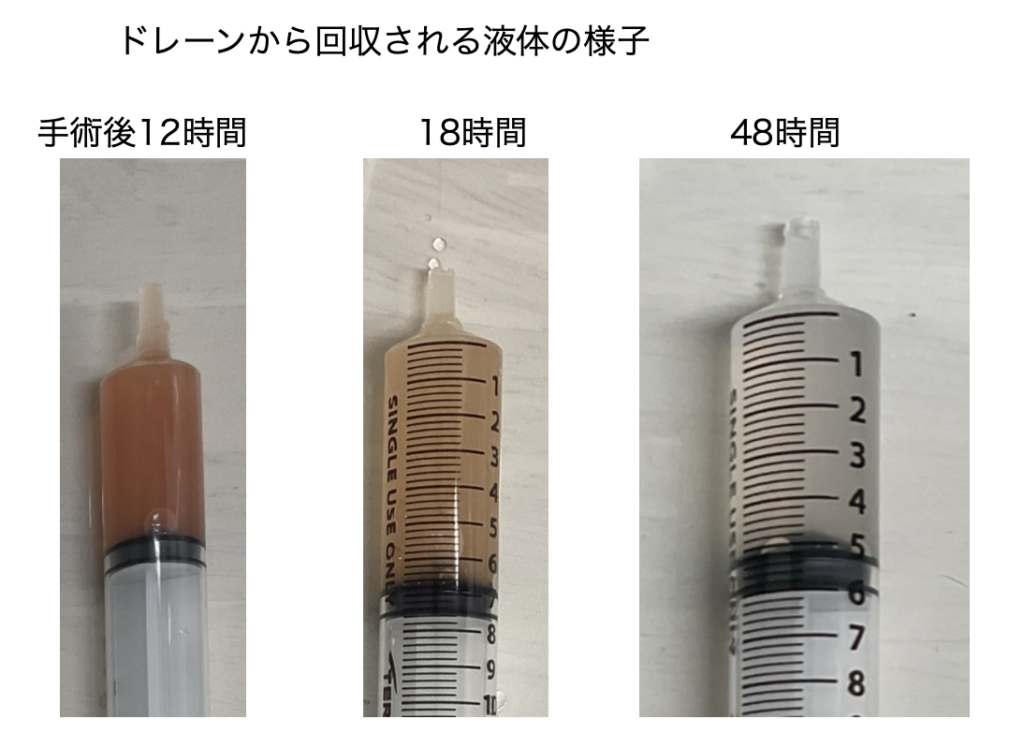

手術時には患部周囲に炎症が波及しており、術後回復が順調に行くかととても心配な状況で、ドレーンを腹腔に設置し、手術終了としました。手術後、お腹の中で出血や炎症を確認するためにドレーン(下の画像でグルグル巻の管)をお腹に固定してします。

ドレーンから回収される液体は手術後2日でほぼ透明になり、体調が回復する傾向が見られたのでドレーンを抜きました。